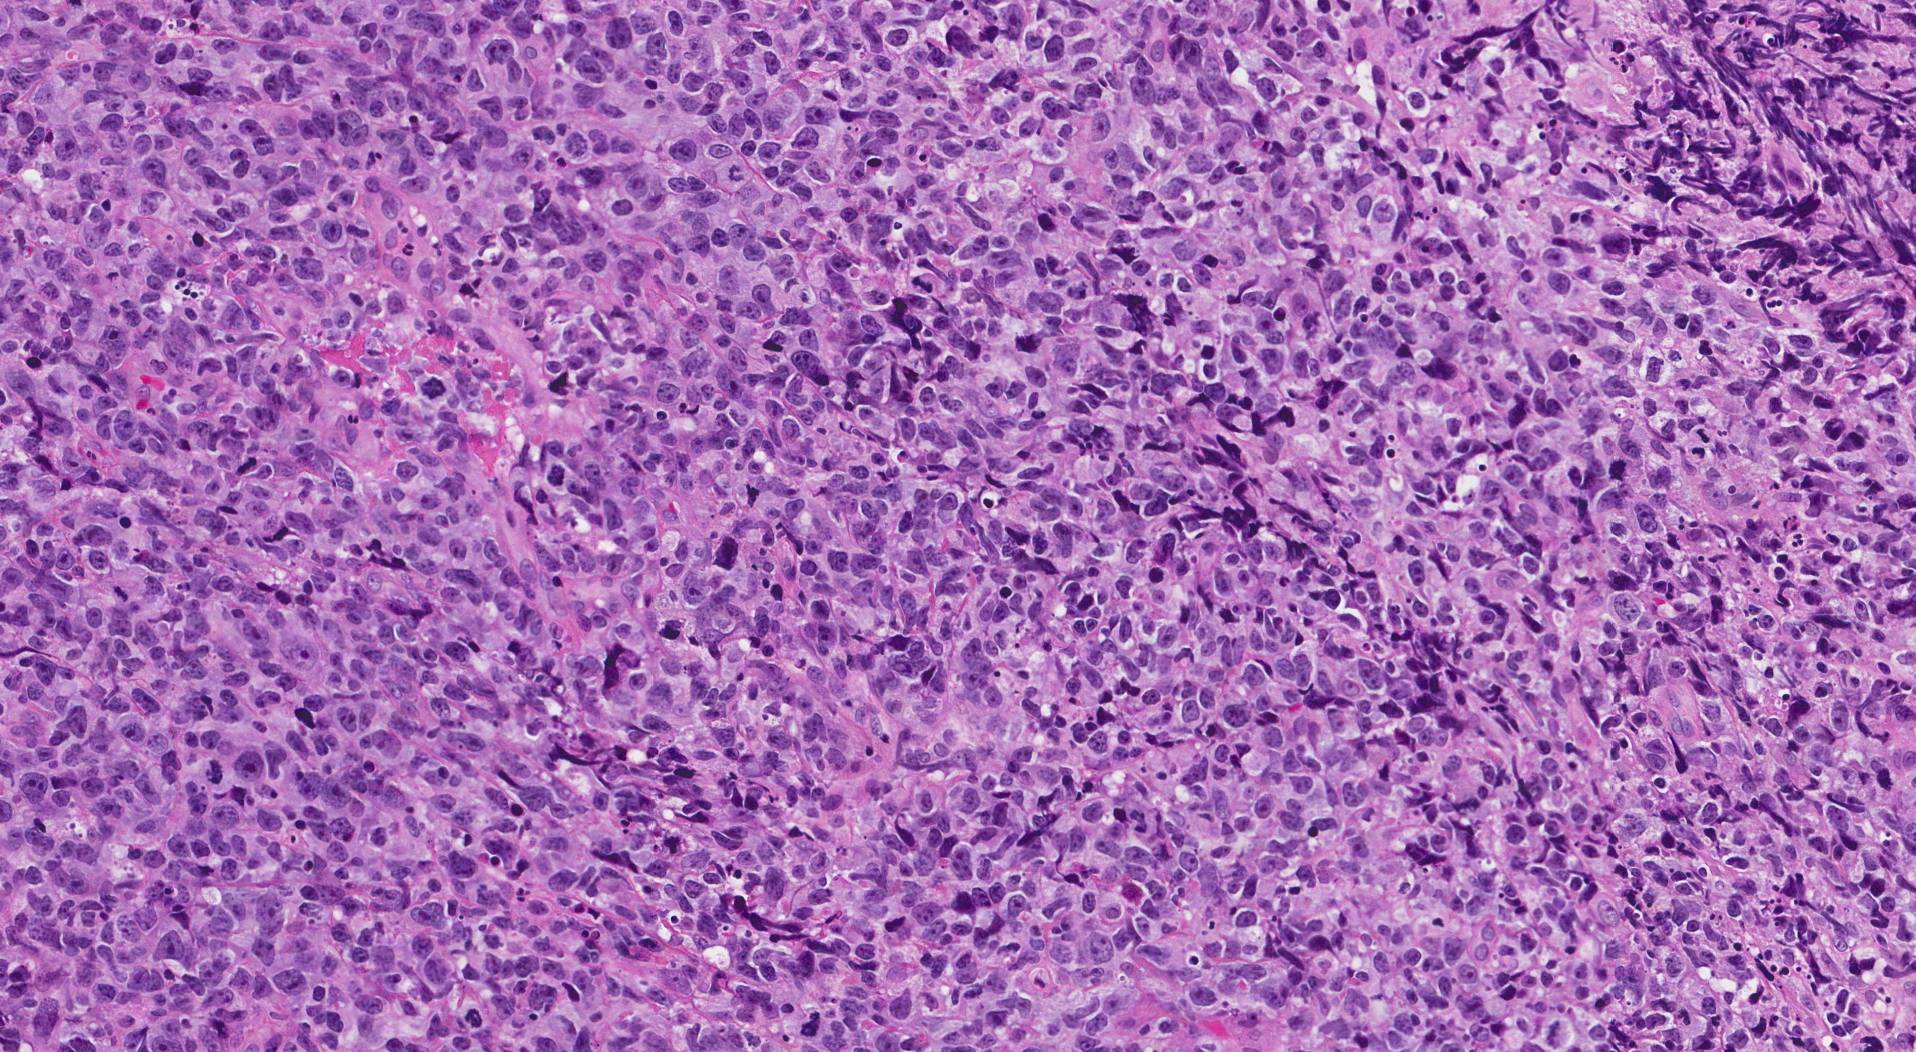

喉の扁平上皮癌は扁平上皮細胞で発生します。扁平上皮細胞は、皮膚、口、喉の内層を構成する平らで薄い細胞です。

喉の扁平上皮がんは、喉の内側を覆う細胞で発生する頭頸部がんの一種です。気管、扁桃腺、または発声器に発生する場合があります。

扁平上皮癌 咽頭癌は喉のあらゆる領域に影響を与える可能性があります。医師は喉の扁平上皮癌を喉内の部位によって分類する場合があります。